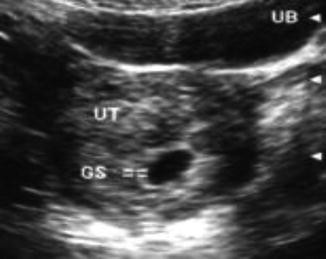

Our affordable early viability private pregnancy scan / 6 week / dating scan is designed to provide you with reassurance in the early stages of your first trimester . We will assess the viability of the pregnancy i .e . visualise fetal heartbeat, assess ectopic pregnancy, vaginal bleeding or pelvic pains & determine if single or multiple pregnancy .

We are Open, Covid-19 Regulations applied . An Early Pregnancy Scan , also called a Viability or Dating Ultrasound scan , will confirm a pregnancy, confirm the gestation age and establish an Estimated Due Date (EDD) . An Early Pregnancy Ultrasound Scan can be performed from 6 weeks of pregnancy at our Harley Street, London clinic or our Alderley Edge, Cheshire clinic .

Early, dating and viability scans (6 - 15 weeks) Why have an early pregnancy scan ? . . . How is the scan carried out? Under 10 weeks the best way to see your baby and get clearer images is by carrying out a transvaginal scan (internal scan ) . However, if you would prefer to come with a full bladder we can start by scanning you this way and the . . .